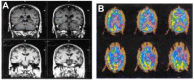

Frontotemporal dementias are neurodegenerative diseases in which symptoms of frontal and/or temporal lobe disease are the first signs of the illness, and as the diseases progress, they resemble a focal left hemisphere process such as stroke or traumatic brain injury, even more than a neurodegenerative disease. Over time, some patients develop a more generalized dementia. Four clinical subtypes characterize the predominant presentations of this illness: behavioral or frontal variant FTD, progressive nonfluent aphasia, semantic dementia, and logopenic primary progressive aphasia. These clinical variants correlate with regional patterns of atrophy on brain imaging studies such as MRI and PET scanning, as well as with biochemical and molecular genetic variants of the disorder. The treatment is as yet only symptomatic, but advances in molecular genetics promise new therapies.